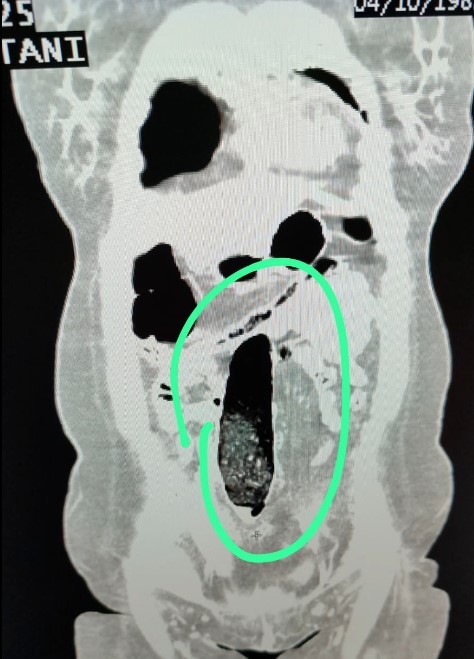

Otobüste bulunan İran uyruklu 2 şahıs üzerinde yapılan ilk kontrollerin ardından, durumdan şüphelenilmesi üzerine şahısların iç beden muayeneleri gerçekleştirildi. Yapılan tıbbi kontrollerde, şahısların vücutlarının doğal boşluklarında ve bağırsaklarında uyuşturucu madde bulunduğu tespit edildi.

Sağlık kuruluşunda gerçekleştirilen tıbbi müdahale sonucunda, F. V. isimli bayan şahıstan 3 parça halinde toplam 397,78 gram metamfetamin maddesi ele geçirildi. S. İ. isimli erkek şahıstan ise 24 adet sentetik hap ile 3 parça halinde toplam 167,68 gram metamfetamin maddesi çıkarıldı.